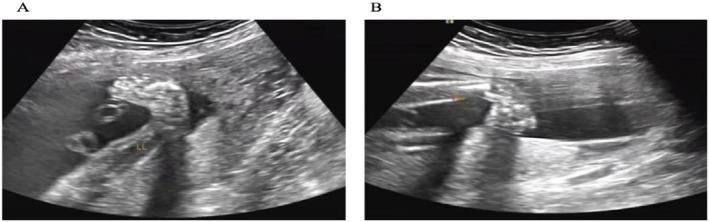

A total of 24,319 pregnant women underwent prenatal diagnosis, and 24 cases were diagnosed with 22q11.2DS, with an incidence of 0.99‰ (24/24319), including 16 cases of congenital heart disease, 4 cases of renal pelvis separation, 3 cases of cleft lip and palate, 2 cases of double strephenopodia, 2 cases of nasal bone dysplasia, and 1 case each of unclear thymus, spina bifida with meningomyelocele, abnormal fetal growth retardation, and NT thickening.

共有24319例孕妇接受产前诊断,24例被诊断为22q11.2DS,发生率为0.99‰(24/24319),其中先天性心脏病16例,肾盂分离4例,唇腭裂3例,双侧马蹄内翻足2例,鼻骨发育不良2例,胸腺不清、脊柱裂伴脊髓脊膜膨出、胎儿生长发育异常、NT增厚各1例。